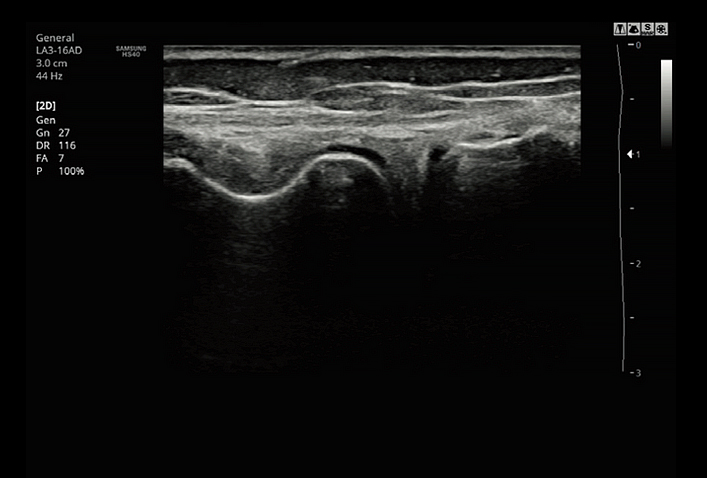

AutoIMT+ is a screening tool to analyze a patient's potential risk of cardiovascular disease. It allows easy intima-media thickness measurement of both the anterior and posterior wall of the common carotid by the click of a button.

LA3-16ADApplication:Small parts, Vascular, Musculoskeletal, Abdomen, Obstetrics, Gynecology, Pediatric, Emergency |